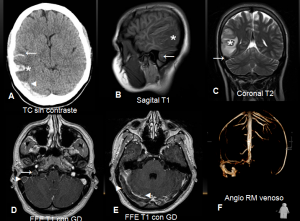

Trombosis de senos venosos durales (seno transverso y sigmoide derechos) e infarto venoso con transformación hemorrágica secundario.

El diagnóstico por TC suele ser difícil de establecer. El seno afecto se ve hiperdenso sin contraste; tras contraste se identifica la ausencia de llenado (signo del delta vacío). En RM el trombo agudo es isointenso en T1 e hipointenso en T2; el subagudo es hiperintenso en T1. La angio-RM venosa confirma el diagnóstico.